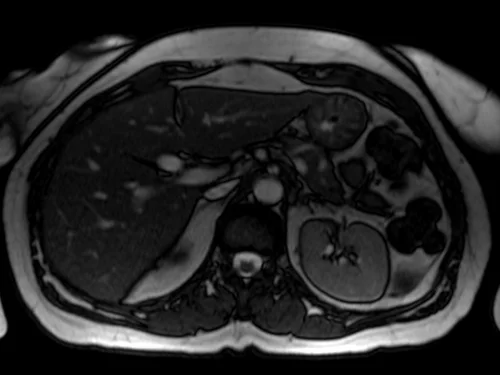

mrcp axial trufi image 2 - MRI